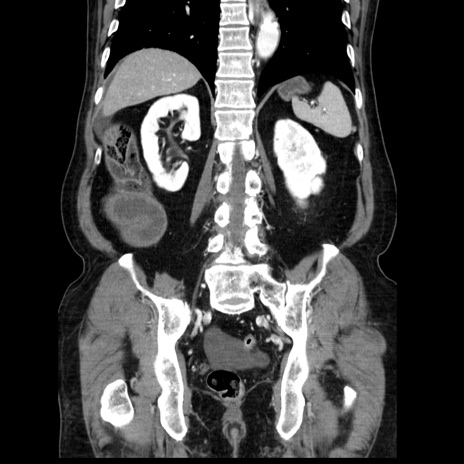

症例30(冠状断像)

【症例】80歳代男性

【主訴】臍周囲痛

【現病歴】約6時間前から臍下部痛が出現。次第に腹部膨隆・背部痛も生じてきたため来院。背部痛の場所は変化しない。

【身体所見】意識清明、BT 36.3℃、BP  131/87mmHg、P 87bpm、SpO2 100%(RA)、臍周囲自発痛・圧痛あり、反跳痛なし、自発痛部位に一致して板状硬あり、腹部膨隆、腸雑音減弱、CVA tenderness両側陰性。

【データ】WBC 19600、CRP 0.33